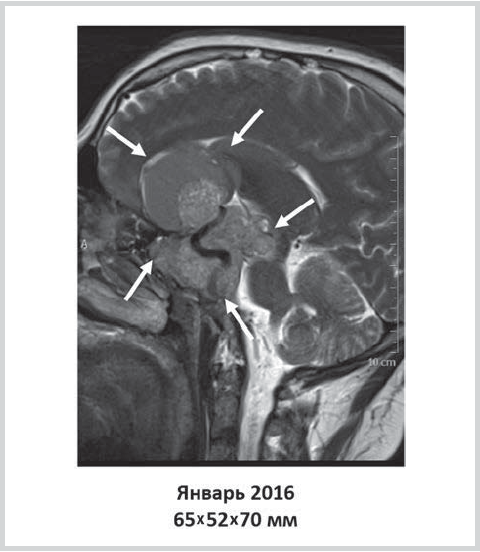

The first complaints of headache appeared at the age of 28. For this reason, brain MRI was performed, which revealed microadenoma of the pituitary gland (44×44×29 mm in size) with extrasellar growth, chiasmal compression, and involvement of the right cavernous sinus. Examination revealed an increase in the blood level of prolactin to 202.8 ng/ml (reference range, 4.0—15.2). The patient was recommended for transcranial adenomectomy followed by radiotherapy, which he refused. The patient neither sought medical help nor received any treatment during the next 8 months. An increase in the intensity of headaches and a progressive decrease in vision served as an indication for second MRI of the chiasmo-sellar region 8 years after the onset of the disease. The repeated examination showed pituitary adenoma of 65×52×70 mm in size with extrasellar growth and involvement of the right cavernous sinus, siphons of both internal carotid arteries, subtotal obturation of the suprasellar cisterns; prolapse of the tumor components into the right half of the basilar sinus and the ethmoidal labyrinth was noted with dislocation of the median brain structures to the left by 5 mm. Blood prolactin level was 15466.0 ng/ml (reference range, 4.9—25.4), macroprolactin level was 1.1%. In order to clarify the diagnosis and select a further treatment approach, the patient was hospitalized in the endocrinology department of the FSBI «V.A. Almazov National Medical Research Centre» of the Ministry of Health of the Russian Federation in January 2016.

Six months after initiation of the therapy with dopamine agonists, the patient reported a decrease in headache and a significant improvement in the overall well-being. According to the brain MRI, there was a positive trend in the form of a decreased size of the formation to 53×50×35 mm (fig. 2).

Fig. 2. Change in the size of pituitary formation 6 months after cabergoline therapy.